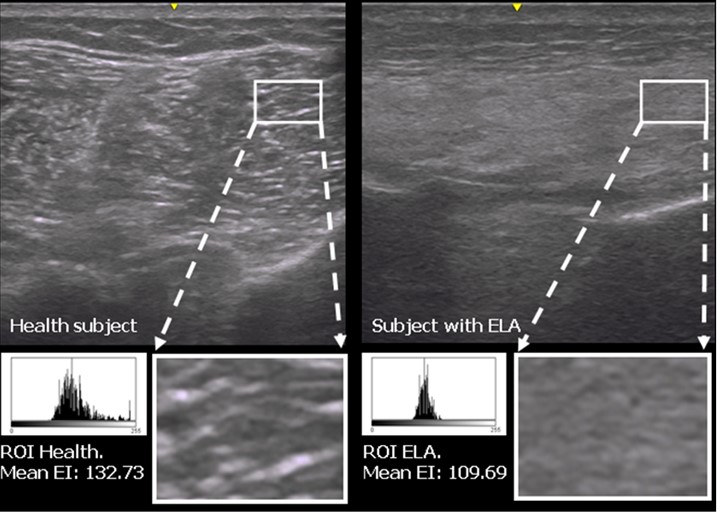

Se trata de un trabajo sobre el desarrollo y la cuantificación de nuevos marcadores ecográficos musculoesqueléticos en pacientes afectados de esclerosis lateral amiotrófica. El trabajo se ha desarrollado en colaboración con investigadores de la Universidad de Murcia, de la Universidad Católica de Murcia y de la Unidad de ELA del Hospital Universitario La Fe de Valencia.